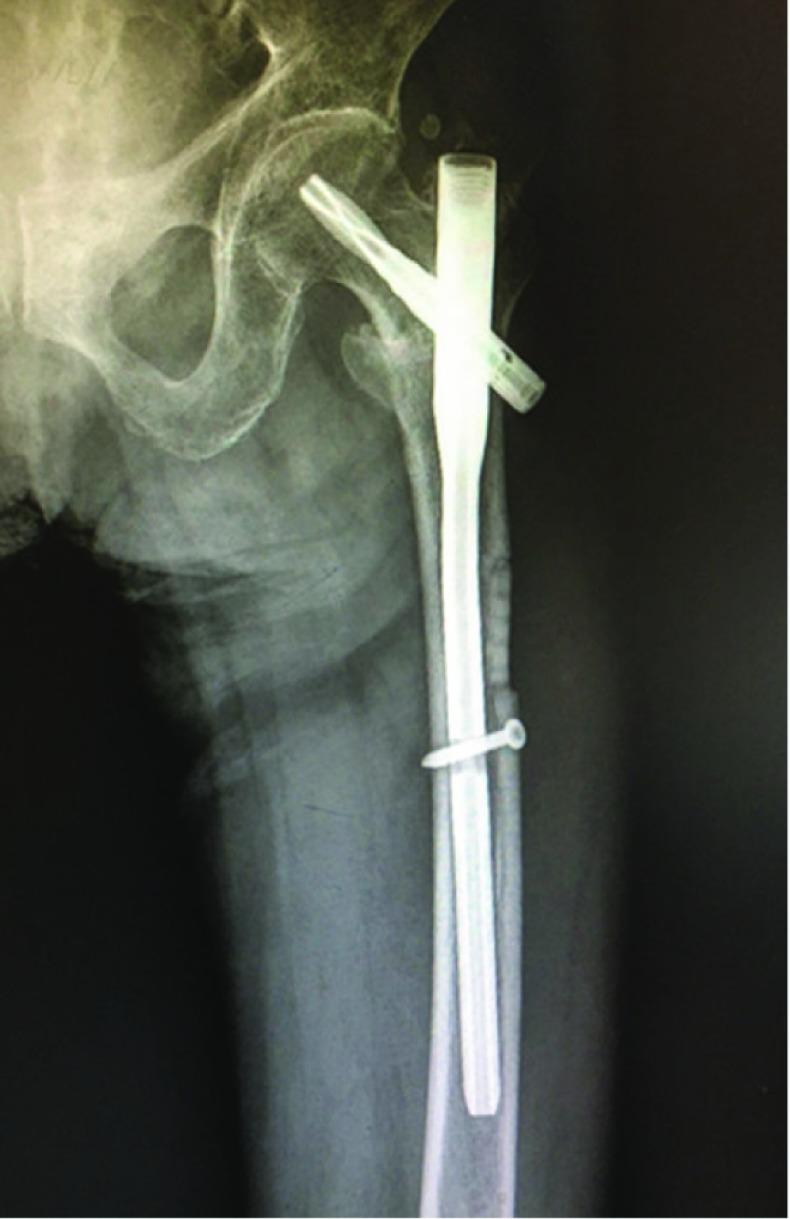

PFNA植入术中取出卡在股骨干的折断扩孔钻:1例报告

Removal of broken reamer stuck into femoral shaft in implanting PFNA: a case report.

Femoral intertrochanteric fracture is very common in elderly population. The usual treatment for these patients is intra-extramedullary fixation. In normal situations, expand medullary cavity is needed, in order to implant various intramedullary implants. On rare occasion, which will in turn lead to the reamer is stuck into the medullary cavity of femoral shaft. Open or closed technique for moving of the broken nails had been reported before. We firstly report a novel technique by using handy tool which included in orthopaedic instrument set to remove the broken reamer stuck into femoral cavity when implanting a PFNA.

股骨转子间骨折在老年人群中非常常见。这些患者的常规治疗方法是髓内固定。在正常情况下,需要扩髓腔以便植入各种髓内植入物。在极少数情况下,这会导致扩孔钻卡在股骨干髓腔内。之前已有关于取出折断钉子的开放或闭合技术的报道。我们首次报告了一种新技术,即在植入股骨近端防旋髓内钉(PFNA)时,使用骨科器械套装中包含的便捷工具取出卡在股骨髓腔内的折断扩孔钻。